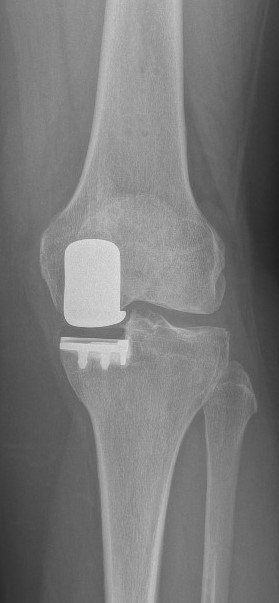

Das Kniegelenk besteht aus drei Gelenkkompartimenten: einem inneren, zentralen und äußeren Kompartiment. Die Kniescheibe bildet ein Widerlager und gleitet über den Oberschenkelknochen. Prinzipiell ist ein isolierter oder kombinierter Verschleiß vom inneren oder äußeren Gelenkkompartiment sowie auch dem Kniescheibenwiderlager möglich. Erkennt man die Erkrankung früh genug und ist der Leidensdruck entsprechend, so kann man die einzelnen Kompartimente isoliert ersetzen.

Wir halten ein großes Portfolio moderner und bewährter Prothesen vor, die sich entsprechend den o.g. Ausführungen vom Prothesendesign unterscheiden. Innerhalb des Designs liegen verschiedene Ausführungen und verschiedene Größen vor, so dass wir je nach Krankheitsbild für Sie eine individualisierte Versorgung anbieten können. Bei entsprechender Indikation kann der Kniegelenkersatz auch mit robotischer Unterstützung erfolgen, die Prinzipien werden in dem nachfolgenden Artikel aus FOCUS-Gesundheit 5/2023 verständlich dargestellt.

Sollte bei Ihnen eine Endoprothese in Frage kommen, wird durch Beurteilung verschiedener Faktoren der Prothesentyp aus dem o.g. Portfolio für Sie ausgesucht.